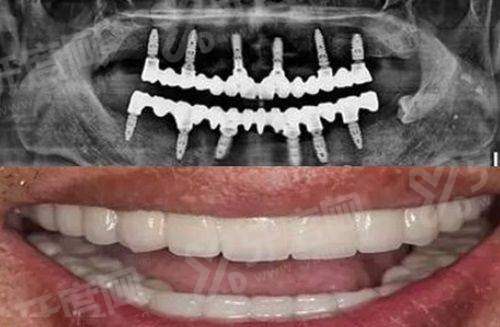

1、术前会用CBCT全方面扫描患者口腔,通过电脑模拟种植的位置、深度和角度,制作专属的数字化导板,提前规避种植风险。

2、手术过程中医生完全依照导板操作,种植误差能控制在极小范围,减少对周围牙齿和组织的损伤,种植后的牙齿稳固性更强。

3、不管是前牙缺失追求美观,还是后牙缺失看重实用性,这种技术都能适配,种植后的牙齿在颜色、形态上和真牙接近,使用感自然。